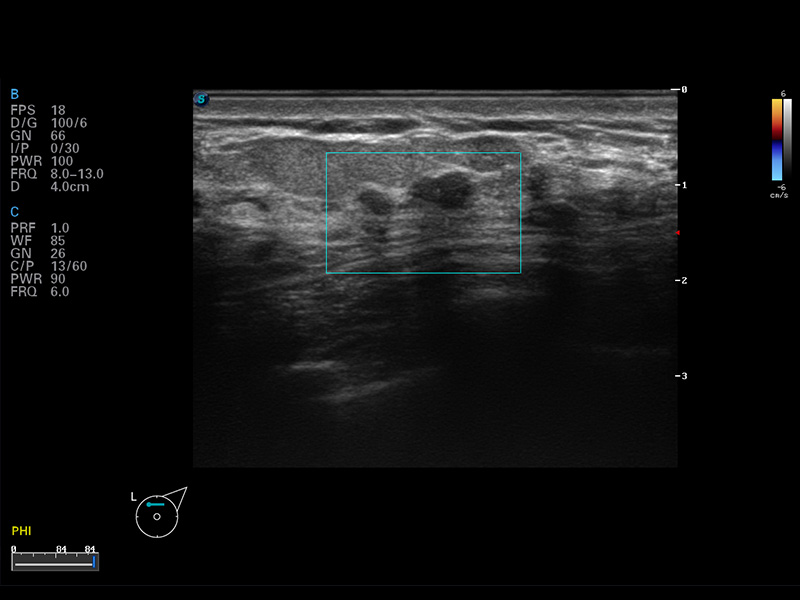

S8 EXP便携式彩色多普勒超声诊断仪是诸侯快讯官网研发的高端全身应用型便携彩超。高通道的VIS平台融合可视化(Visual)、智能化(Intelligent)和人性化(Smart)的特点,配以诸侯快讯官网自主研发生产的探头大家族,使您能够快速、准确的获得病人信息,提高工作效率的同时减轻疲劳。

成像技术

空间复合成像